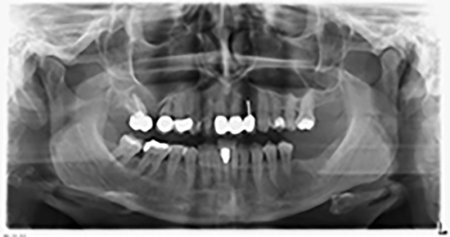

Orthopantomogram

Image 20: Orthopantomogram after treatment

Sky implants supplied by bredent were implanted – tooth 16: 5.5 x 10mm and tooth 14: 4.0 x 10 mm.